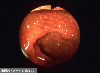

Comparative diagnosis of inflammatory disease at the boundary region of the digestive tract.

Endoscopy